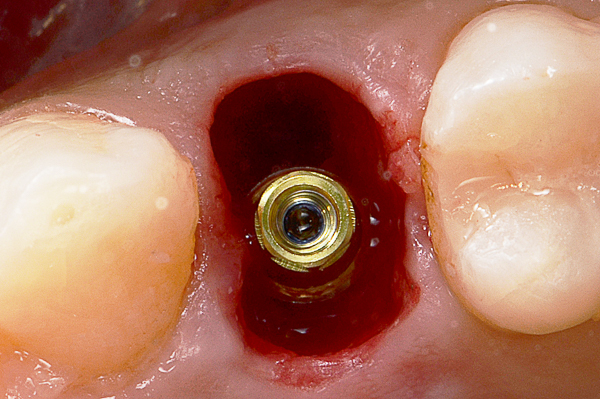

Il caso presenta la riabilitazione di un premolare superiore interessato dal fallimento di un trattamento endodontico in una paziente donna di 37 anni, non fumatrice e con una buona igiene.

A seguito dell'analisi radiografica viene pianificata l'estrazione atraumatica del premolare con l'inserimento contestuale di un impianto Shelta. La riabilitazione immediata viene eseguita con un pilastro XA per protesi avvitata, su cui viene fissato un provvisorio realizzato in laboratorio secondo i principi dei profili di emergenza della tecnica B.O.P.T.

Donna, 37 anni, non fumatrice, con una buona igiene, si presenta in studio con un fallimento del trattamento endodontico dell'elemento 1.4.